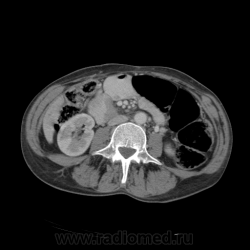

КТ ОБП - гепатомегалия, признаки панкреатита

МРТ ОБП - от 16.12.10 гепатомегалия, расширение панкреатических протоков.

Похоже на то, что все было списано на калькулезный холецистит. Наши морфологи пересмотрели стекла с гистологией и окончательно написали о наличие высокодефференцированной аденокарциноме. У меня только две мысли образования исходит из БДС или первичный рак 12п.к., хотя сейчас гадать бесполезно. 12п.к. циркулярно сужена.